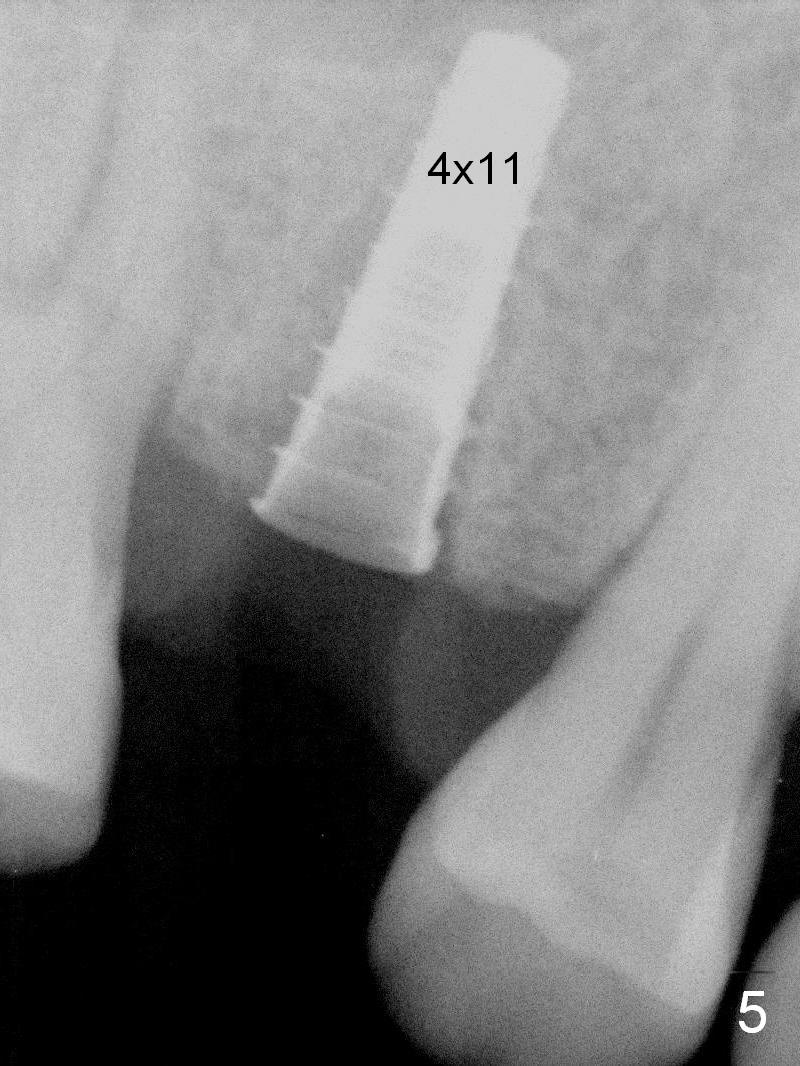

A 47-year-old man returns emergently with subgingival fracture of the lingual (L) cusp of the tooth #4 (Fig.1-3). After extraction (no bony defect) without drilling, a 4x11 mm dummy implant is placed as a tap drill with satisfactory stability (Fig.4,5). To get subcrestal placement, a shorter (4x9 mm) implant is inserted with insertion torque of < 35 Ncm. In retrospect, a larger implant (4.5 mm) would be better in term of primary stability. After allograft placement into the buccal and lingual gaps, a 4.5x4(4) mm abutment is placed for an immediate provisional. There is a peri-implant gap 7 months postop (Fig.7<, as compared to the implant at #2 (6 months postop)) . When the loose abutment is being retightened, the patient feels pain, although the gingiva appears healthy (Fig.8). A larger implant should have been used; the abutment should have been removed. The implant dislodges while the abutment is untightened 8 months postop. The osteotomy is found intact. A 4.5x11 mm dummy implant is placed 2 mm subgingival with 20 Ncm (Fig.9). When a 4.5x11 mm definitive implant is placed 3 mm subgingival (Fig.10,11), torque reaches 50 Ncm. A 5.5x3 mm healing abutment is placed. Three months postop, the implant is stable (Fig.12,13) and impression is taken.